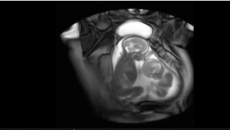

Една трудница решила да појде на ехо бидејќи последните денови чувствувала невообичаена мешаница во својот стомак. Тоа...